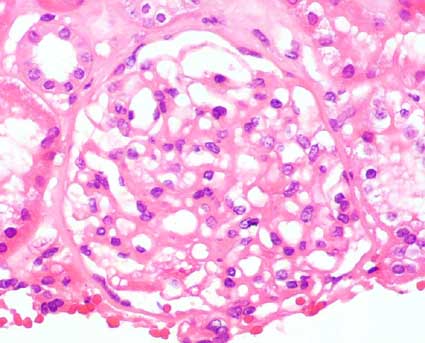

Figure 2.

Some glomeruli appear almost normal (H&E, X400).